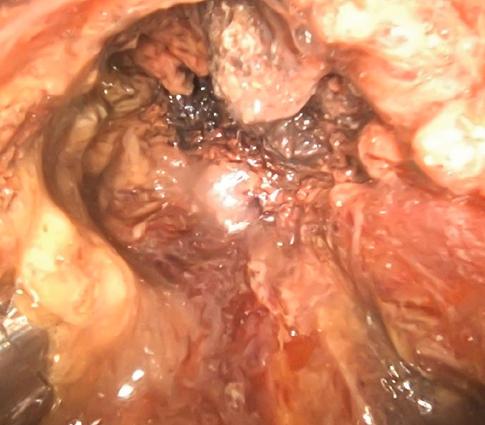

Direct Endoscopic Necrosectomy (DEN)

Can be employed, along with endoscopic drainage, to treat walled-off pancreatic necrosis (WOPN) after acute pancreatitis.

•Facilitates increased aspiration for removal of necrotic material

•Allows for use of large-caliber instruments for debridement and TTS stents